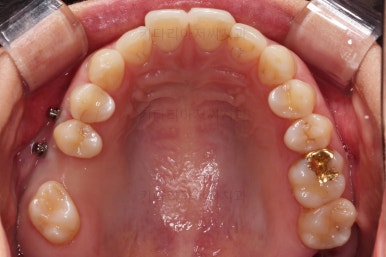

X-ray로 봤을 때 빈 공간에는 여러 가지 문제가 있었는데요.

뒷니가 쓰러졌다.

공간이 잠식 당했다.

어금니 위쪽 공기주머니가 잇몸뼈를 갉아먹으면서 잇몸뼈가 매우 얇아져있다.

어금니쪽은 쓰러진 어금니를 원위치 시키기 위해서 미니스크류를 식립하여 준비작업을 해줍니다.

진행상황을 X-ray로도 확인해 줍니다.

적절한 공간 확보 이후 해당 부분의 뼈가 너무 얇아 임플란트를 하기에 부적절했던거죠.

상악동 거상술 + 골이식을 광범위하게 꽤 많은 양을 하고, 한참을 기다립니다.

이후에 적절한 시기에 임플란트 식립을 하고 보철을 하고 마무리를 합니다.